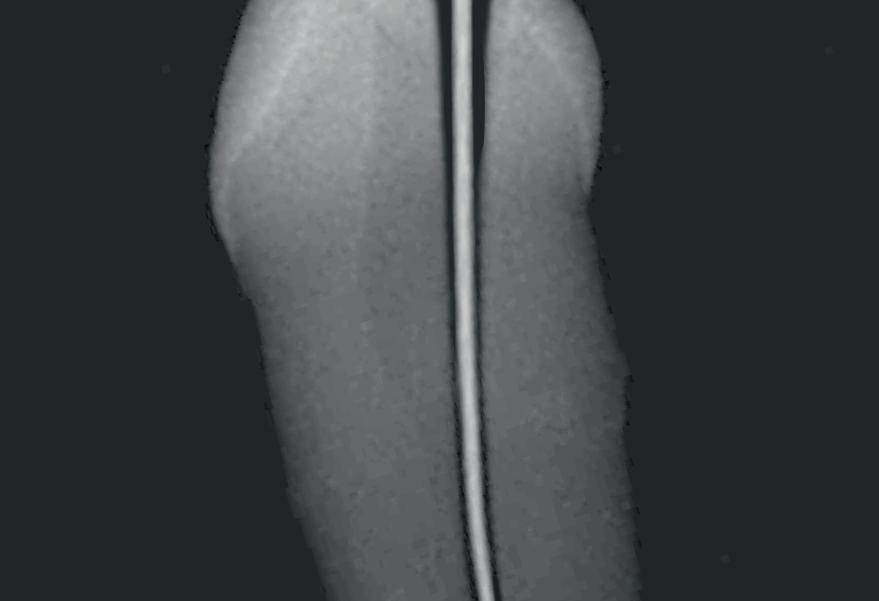

Tri Auto ZX2+

CCW CW CW CCW File example Mode Sequence CW CCW 3